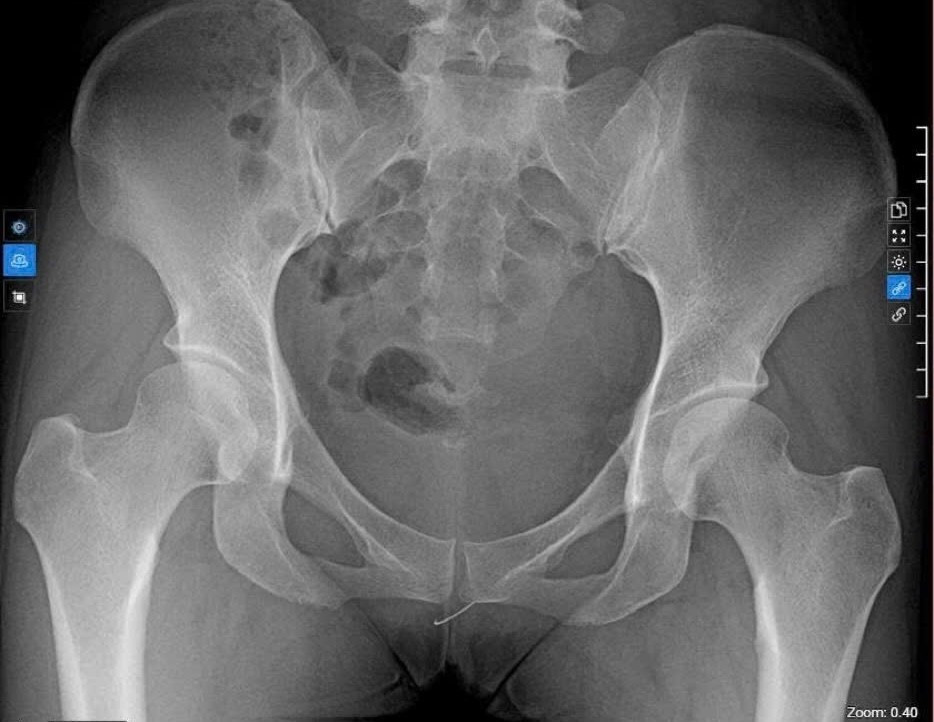

Chụp X-Quang, phát hiện đoạn kim gãy nằm ở tầng sinh môn.

Qua chụp X-quang khung chậu và siêu âm đầu dò âm đạo, các bác sĩ phát hiện một dị vật kim loại nằm tại vùng tầng sinh môn. Sau hội chẩn liên khoa, ê-kíp đã tiến hành can thiệp, lấy ra một đoạn kim khâu nằm ở vị trí hướng 7 giờ tầng sinh môn.